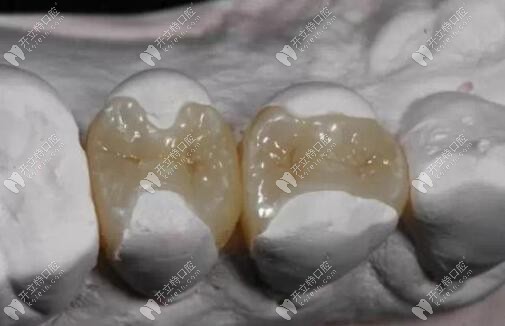

嵌體圖片

嵌體

嵌體補(bǔ)牙圖片

嵌體補(bǔ)牙

而嵌體是口內(nèi)取模,然后技工根據(jù)模型制作與牙洞大小相當(dāng)?shù)那扼w,然后再由臨床醫(yī)生將其戴入牙洞,粘固形成的。